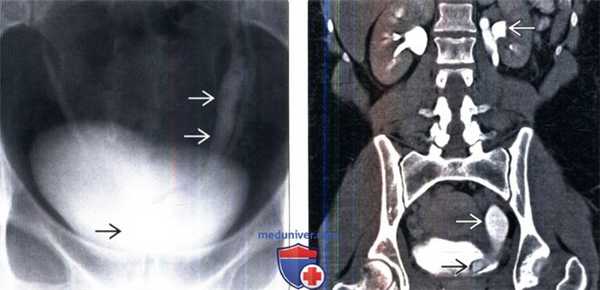

3. Рентгенография при уретероцеле:

• Экскреторная урография (ЭУГ)/цистография:

о Ортотопическое уретероцеле: деформация в виде «головы кобры»:

- Расширенный дистальный отдел мочеточника, выдающийся в просвет мочевого пузыря с окружающим рентгенонегативным ореолом

о Эктопическое уретероцеле: гладкостенное, рентгенонегативное внутрипузырное образование, преимущественно в области основания мочевого пузыря:

- Может выворачиваться в фазу опорожнения и имитировать дивертикул

- Контрастирование просвета зависит от функционирования верхней лоханки

- Симптом завянувшей лилии: смещение контрастирован-ной при рефлюксе нижней лоханки расширенной верхней лоханкой

- При микционной цистоуретрографии может также визуализироваться рефлюкс в нижней лоханке удвоенной системы

4. КТ при уретероцеле:

• КТ с контрастированием:

о Тонкостенное внутрипузырное кистозное образование в пузырно-мочеточниковом сегменте (ПМС)

(Левый) При микционной цистоуретрографии визуализируется округлый дефект наполнения в мочевом пузыре, указывающий на уретероцеле.

(Правый) На фронтальном Т2-взвешенном МР срезе визуализируется удвоенная система левой почки с расширенной верхней лоханкой и сдавливанием нижней лоханки/ Верхняя лоханка переходит в значительно расширенный и извитой мочеточник? оканчивающийся внутрипузырным уретероцеле.